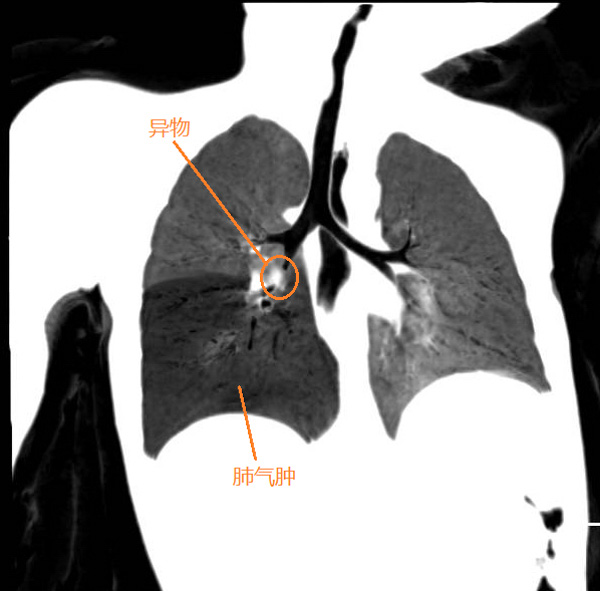

今年正月期間,正是舉國上下防控新冠肺炎的最緊張階段,很多醫院對呼吸道的侵入性手術“談虎色變”。就在那時,一張他帶著防護眼鏡跪在地上為一名1歲患兒手術的照片讓不少人為之動容。磨賓宇說,患兒2天前在家吃橘子后,出現了煩躁、哭鬧、拒食等表現,輾轉了好幾個醫院,到我院時已經精神萎靡,呼吸稍顯急促。檢查發現患兒出現右肺氣腫,高度懷疑支氣管異物。

病情容不得猶豫,職責不允許退縮。身為主診醫生的他第一時間聯系麻醉、手術室團隊做好嚴格防護措施,患兒入院后的2小時,凌晨1點左右患兒被送進了手術室。因為麻醉和手術都必須經過患者氣管,所以氣管異物手術不能像常規手術一樣插管麻醉后再從容的操作。加上兒童的氣道狹窄,視野狹小,手術風險大,手術成敗與窒息死亡往往就在2-3分鐘之間,業內形容為“走鋼絲的手術”。

情況緊急,他當機立斷,直接雙膝跪在地上為患兒進行了手術,不到2分鐘時間,患兒氣管內的異物被成功取出,小朋友的氣緊立即緩解。他發現異物并不是橘子,而是一粒直徑僅有3mm已經灰暗變軟的花生仁,通過詢問家長才知道,7天前小朋友吃過花生。